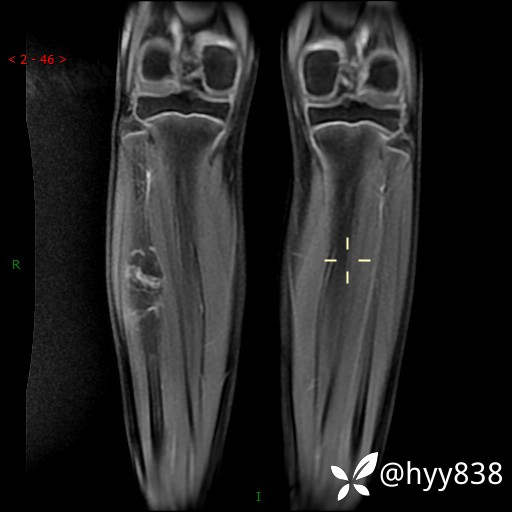

MRI 增强(cor+sag+axi)